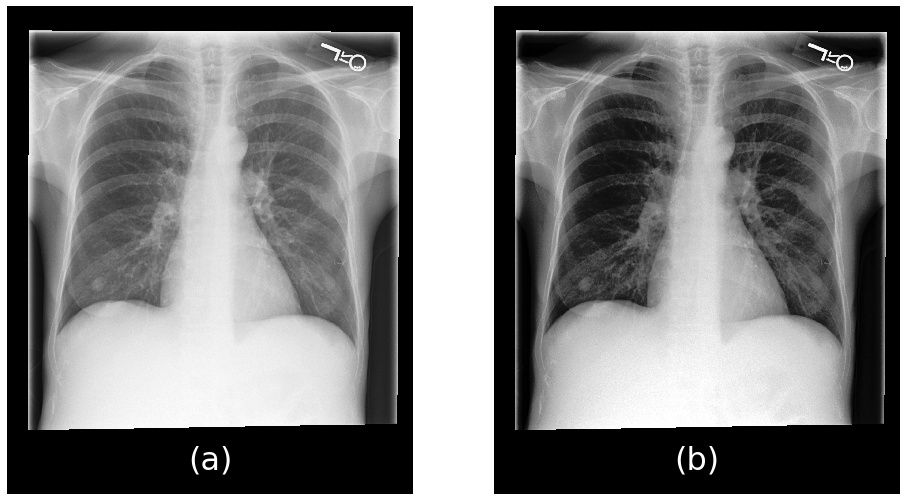

Note that, aside from de-identification and conversion to JPEG, no filtering or processing of the images was performed. Figure 1 provides a comparison of an image read directly from the DICOM and the histogram equalized JPEG format file. The default parameters were used to display the DICOM image.

Figure 1: Example of an image converted from DICOM (a) to JPEG (b).